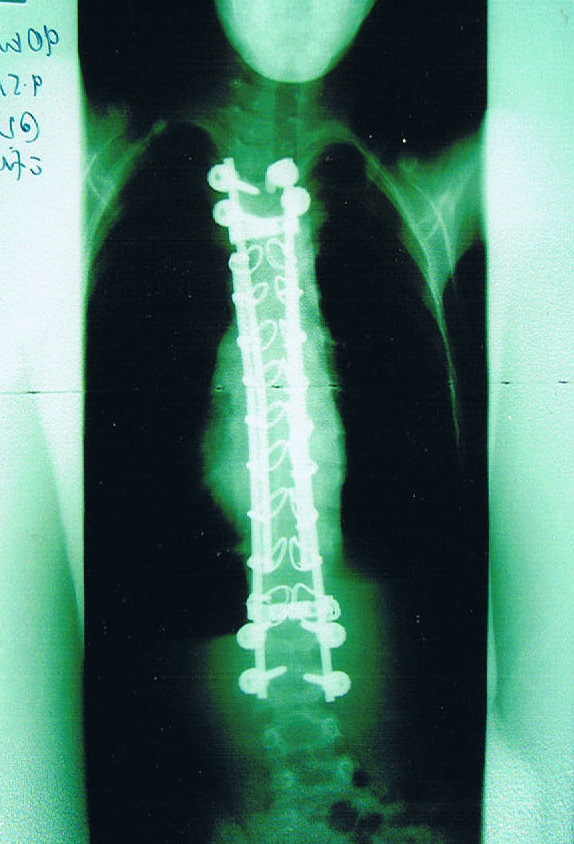

Growing Rods - Single or Dual

The theory of growing rods is to allow for continued, controlled growth of the spine. This is done along the back of the spine. One or two rods span the curve under the skin along the length of the spine. The rods attach to the spine at the top and bottom of the curve with hooks or screws. The curve is not fully corrected, but 'controlled' whilst the child is still growing. They then return every six months to have the rods lengthened via keyhole surgery.

There are a number of possible complications. For example, hook or screw dislodgement, rod breakage, infection, high sensitivity and poor healing of wound site for recurrent lengthenings. A family I have contact with in the US have an 8-year-old who has gone through 8 surgeries in 2 years due to rods breaking and screws loosening etc.